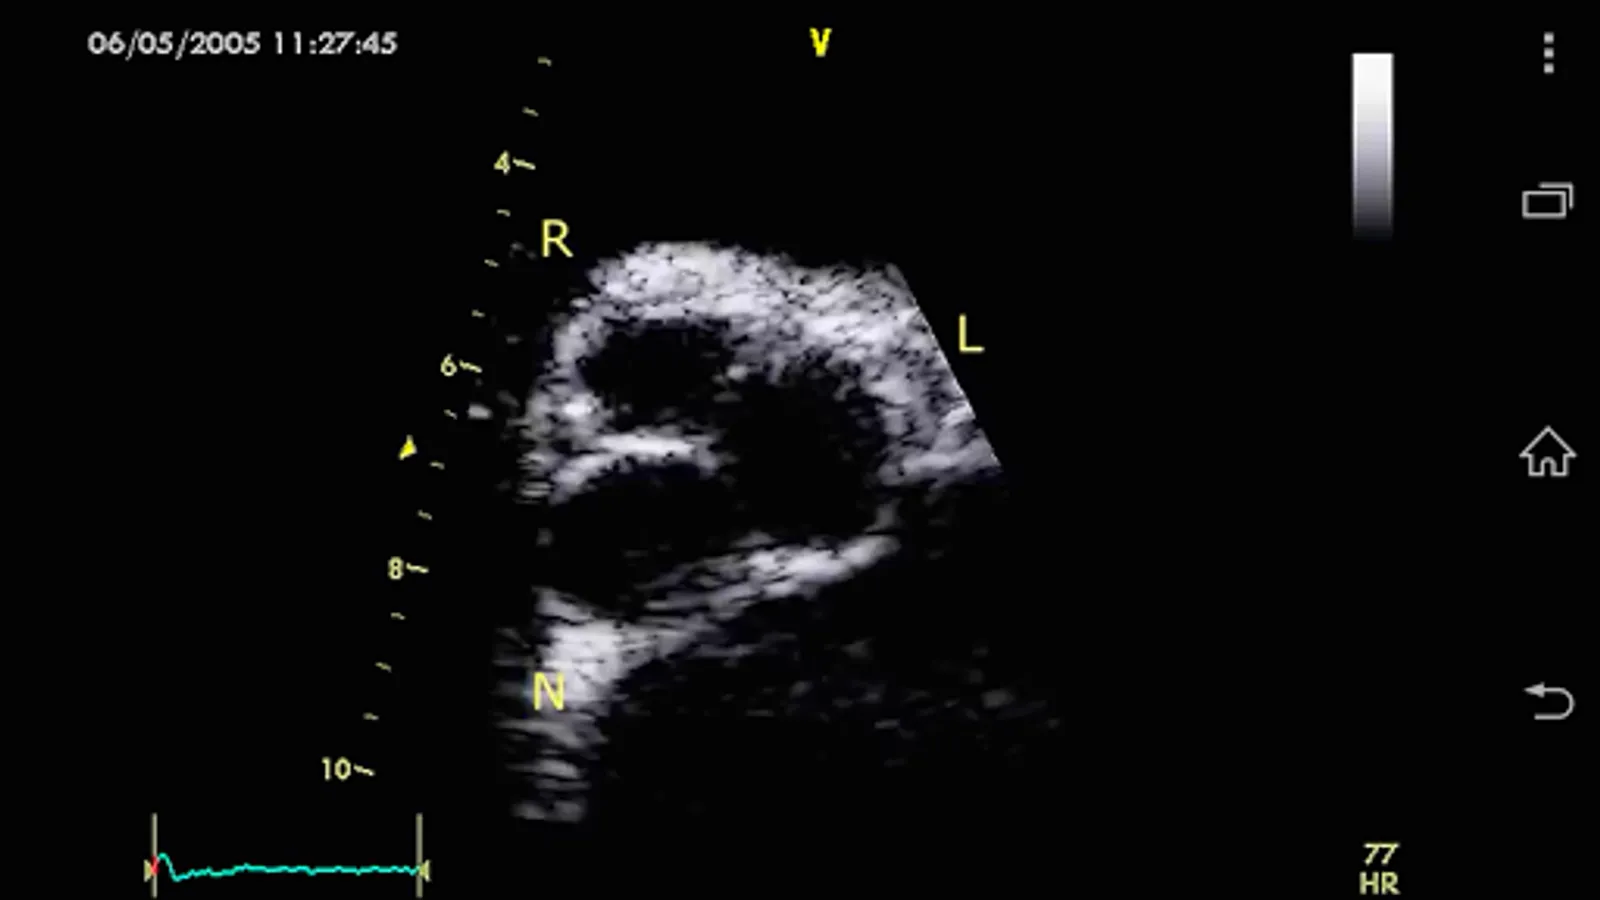

CARDIO3® Comprehensive Atlas of Echocardiography (ISBN 80-969114-8-1) - reference/learning tool for cardiologists, cardiac surgeons, internists, other physicians, and sonographers evaluating echocardiograms for ultrasound diagnosis.